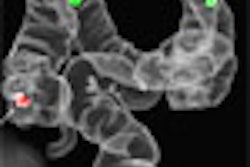

![]() |

| Fourteen-year-old boy with camptodactyly-arthropathy-coxa vara-pericarditis (CACP) syndrome. Anteroposterior radiograph of pelvis shows smooth flattening of femoral heads and acetabulae are irregular. Initial cursory examination may suggest erosive change; however, presence of large acetabular cysts, particularly on the left (arrows) is virtually pathognomonic of CACP syndrome and is highly unusual in juvenile idiopathic arthritis. Note also bilateral coxa vara, which is a feature of condition. |

Some highly distinguishing features of CACP syndrome are intraosseous fluid-filled herniations affecting the acetabulum that appear on x-rays as benign radiolucent acetabular lesions.

"The characteristically large acetabular cysts that occur in CACP syndrome are not seen in juvenile idiopathic arthritis," the authors noted. Also unlike JIA, the cervical spine in CACP syndrome remains normal.